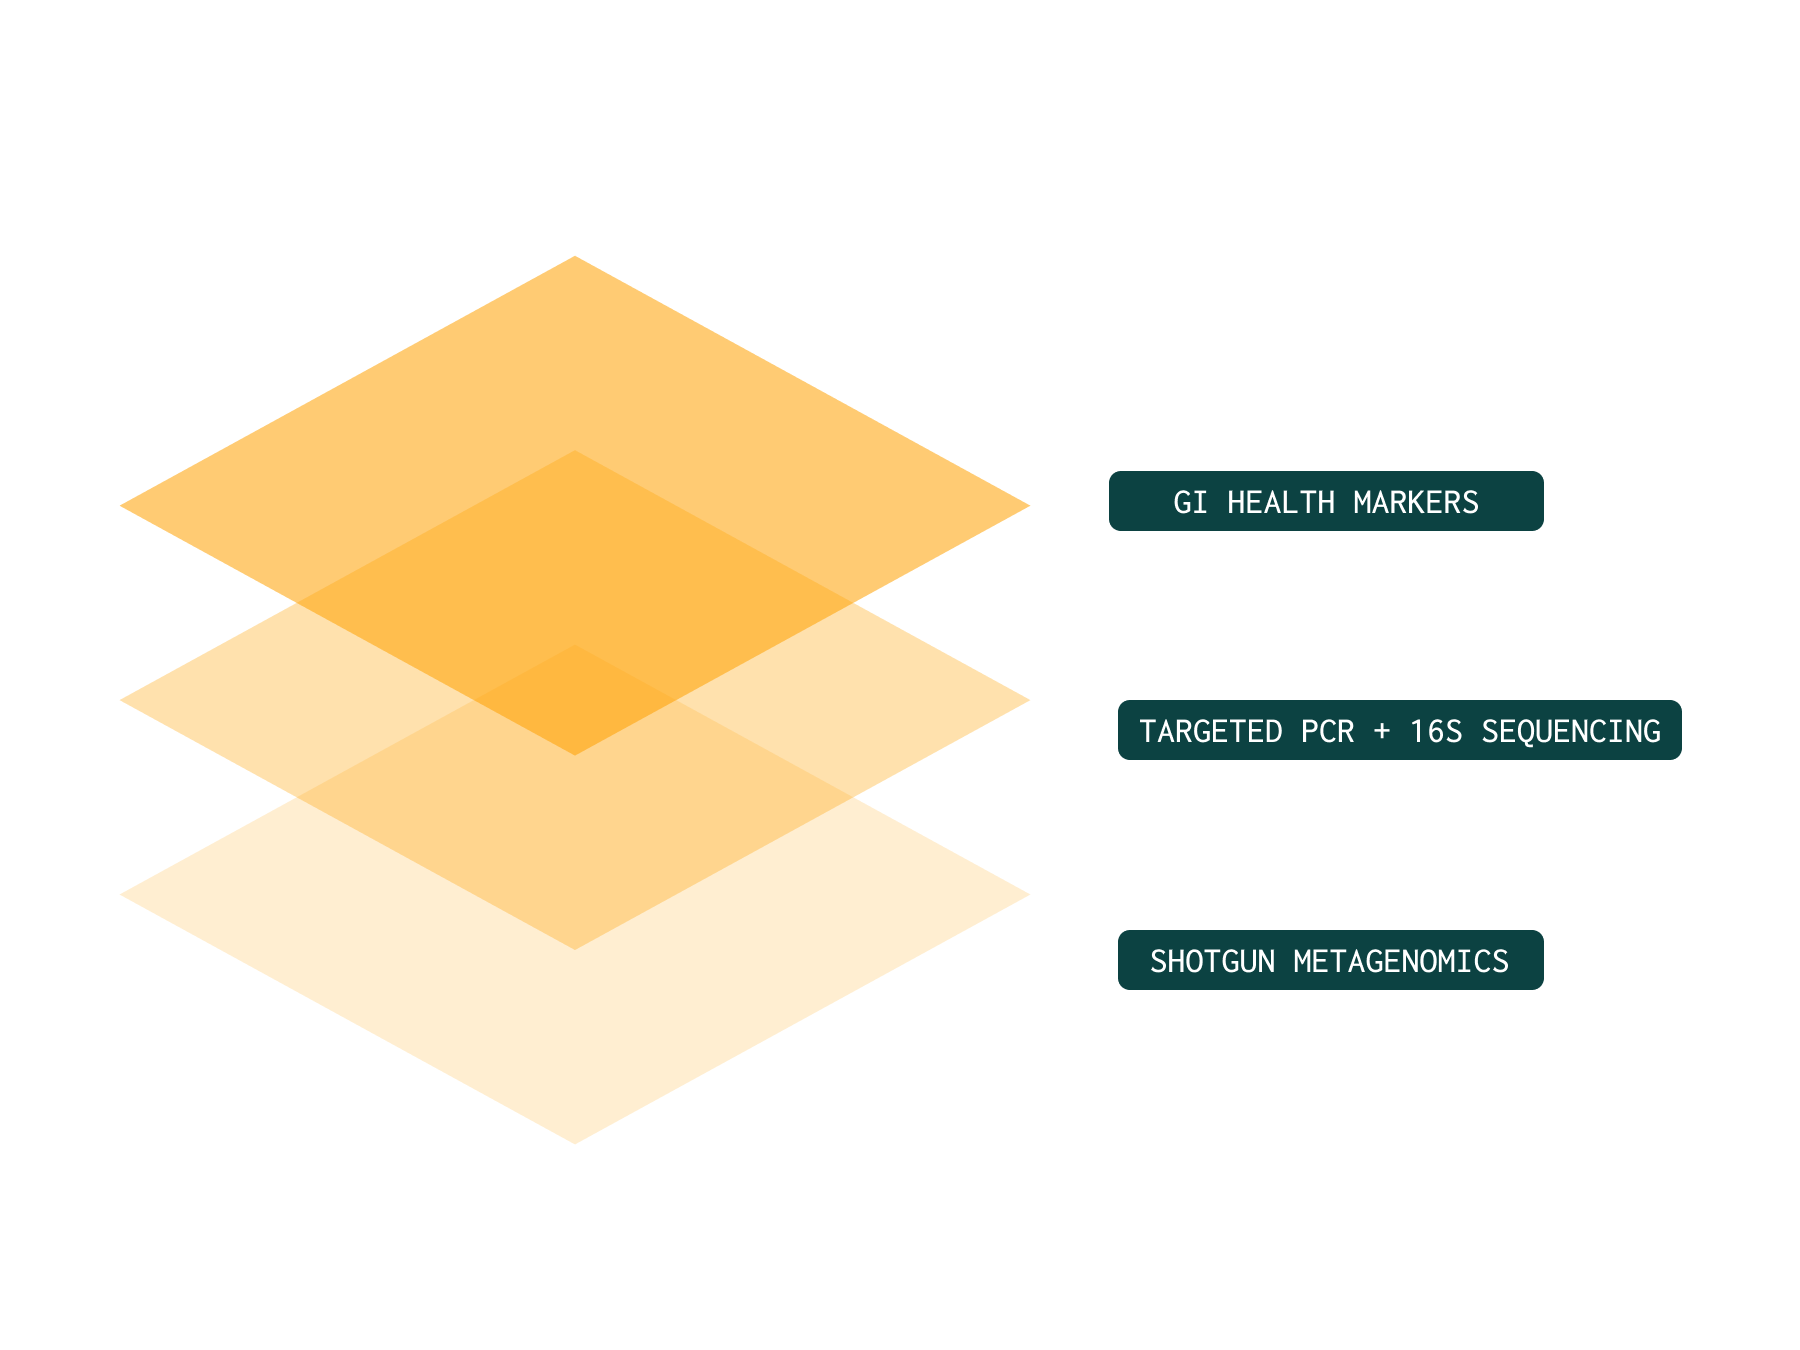

The most accurate picture requires the right combination of technologies

No single method answers every clinical question.

To deliver true ecosystem insight, testing must integrate:

Shotgun metagenomics for full community and functional capacity⁵

Validated Gut health markers to assess gut barrier function and inflammation

PCR for targeted pathogen confirmation